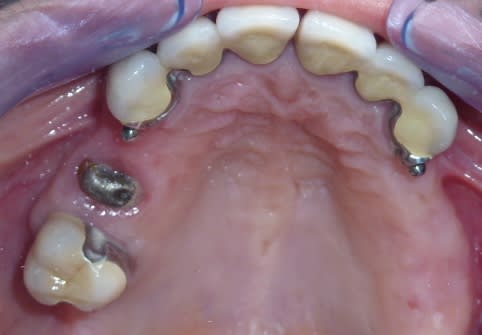

Mais la, apres 1 an de traitements reguliers, entre les lambeaux d'assainissements, les élongations coronaires et les reprises de traitements pourrave j'ai enfin BOUCLE CE CAS !

A l'origine le patient ne voulait surtout pas touché aux dents encore " saine" car il les trouvait bien.

mg 0006 q8ps9i - Eugenol

mg 0012 dzxsrt - Eugenol

mg 0062 jbf6xl - Eugenol

mg 0071 p9nvgl - Eugenol

mg 0005 yv3r8e - Eugenol

mg 0207 xwjxcl - Eugenol